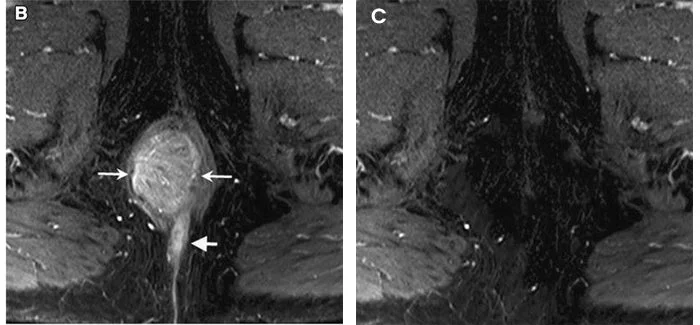

I’ve battled hemorrhoids for years—using sprays, pills, and even sitz baths with little success. But this spray changed everything. In just two days, the itching was gone, and after a week, the swelling had completely subsided. It’s so easy to use; I don’t even need to touch the affected area. What really shocked me was the before-and-after scans—my doctor showed me the difference on the MRI, showing a significant decrease in inflammation. This product has truly changed my life.

After years of suffering from pain and trying every spray, suppository, cream, and natural remedy on the market, I was honestly skeptical at first. But this cream lived up to its promise—fast relief and real, lasting healing. Within days, the pain and swelling began to subside. What completely convinced me was the follow-up scan my doctor showed me—the inflammation was significantly reduced compared to the previous scan. This is the first product I’ve used that truly works, and I finally feel like I’ve had my life back.